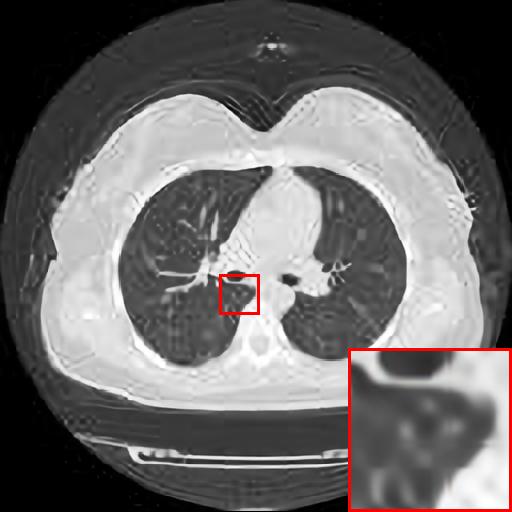

Figure 5: Reconstruction results of each algorithm for low-doze chest CT images.

Figure 6: Reconstruction results of each algorithm for low-doze chest CT images.

III-D Super-resolution Reconstruction of Low-dose CT images

Medical pictures, such as computed tomography (CT) scans, are widely used in clinical applications such as noninvasive illness detection, anatomical imaging, and treatment planning, all of which need judgment while doing CT scans. These imaging approaches, however, have some drawbacks. During CT scans, for example, radiation damage is unavoidable. Low-dose CT (LDCT) is currently the clinically recommended strategy for preventing irreversible radiation harm to the body, however it comes at the cost of getting CT pictures with low resolution or noise contamination. The spatial resolution is generally coarser than that of CT imaging in order to get images with a high signal-to-noise ratio. As a result, obtaining high-resolution scanned images with a low-dose CT scanner is now a challenge.

In this section, we selected chest CT images of COVID-19 patients in an actual hospital [26] for our experiments. The visualization results of the experiments are shown in Figure 5 and Figure 6. The experimental results show that our proposed T-GAN is also applicable to the super-resolution reconstruction of low-dose CT images, and the high-resolution images obtained by our model have more detailed information compared with the baseline algorithm.